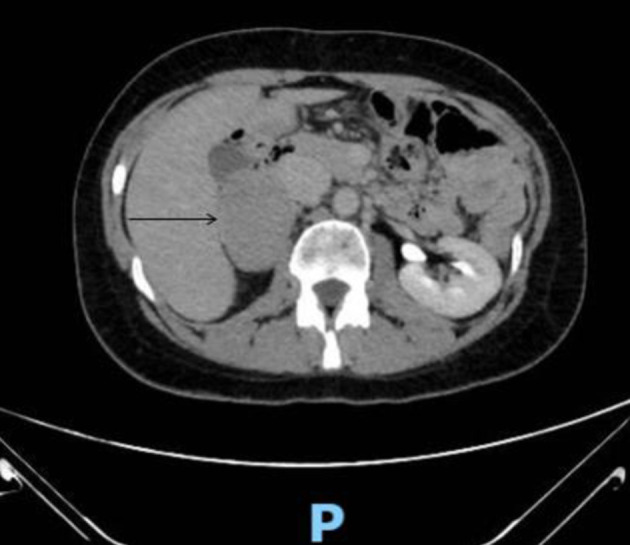

Abstract Image